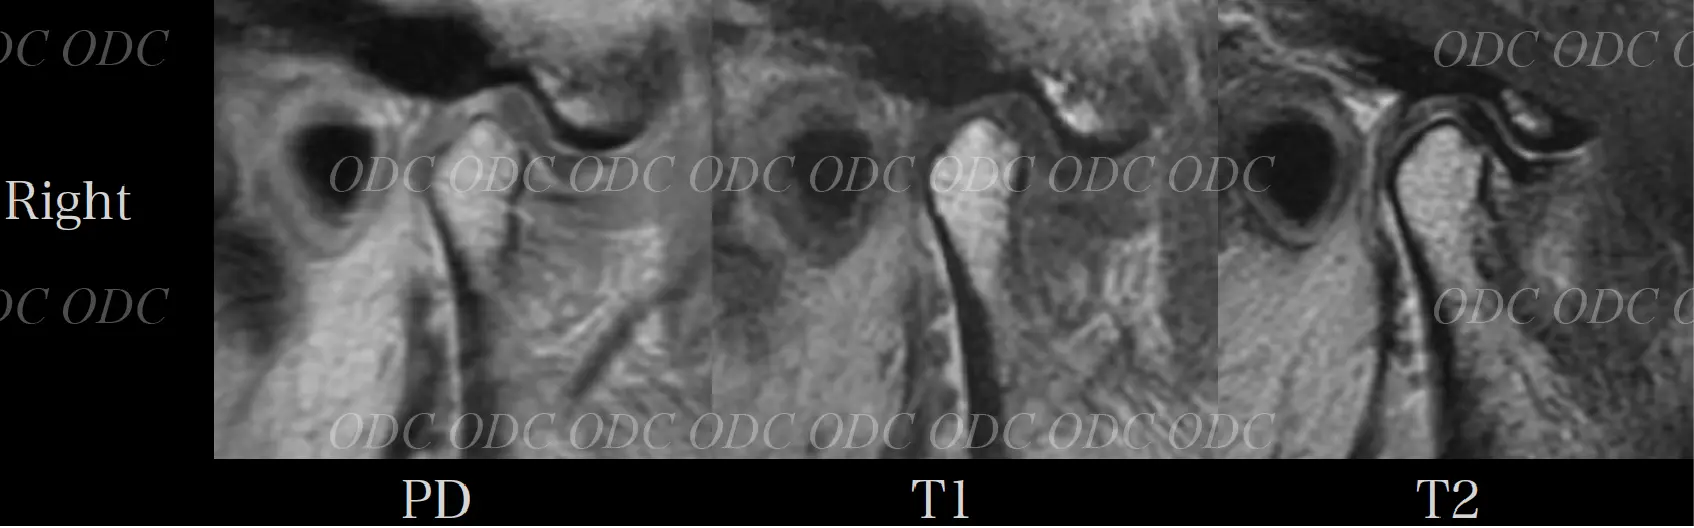

57歳女性。

上顎左側の補綴物の脱離及び全顎的な咬合機能不全を主訴に来院された。

問診をとると、左右顎関節に時々痛みを感じる。

頭痛や肩凝り等の症状も時折みられていた。

多数歯欠損であり、不良補綴物が多く目立つ。過蓋咬合を呈しており、下顎の前方運動に制限があることが推察される。

円板後部結合組織は繊維化を示し、偽円板化を示している。右側で顕著である。

両側下顎頭に骨髄信号の異常は認められない。両側関節円板は前方転位をしている。

初診時に患者が訴えていた顎関節部の痛みはこれによるものと思われる。

両側上下関節腔に貯留が認められ、特に右側で顕著である。

両側関節円板は前方転位をしている。後部結合組織は両側共にさらに偽円板化が亢進したことが分かる。両側上下関節腔に認められていた液貯留がほぼ消失した。

定期的にMRIを撮影し、顎関節の状態を把握しながら治療を進めてきたので、咬合再構成による顎関節への大きなダメージを与えることなく治療を完了することが出来たと考察した。